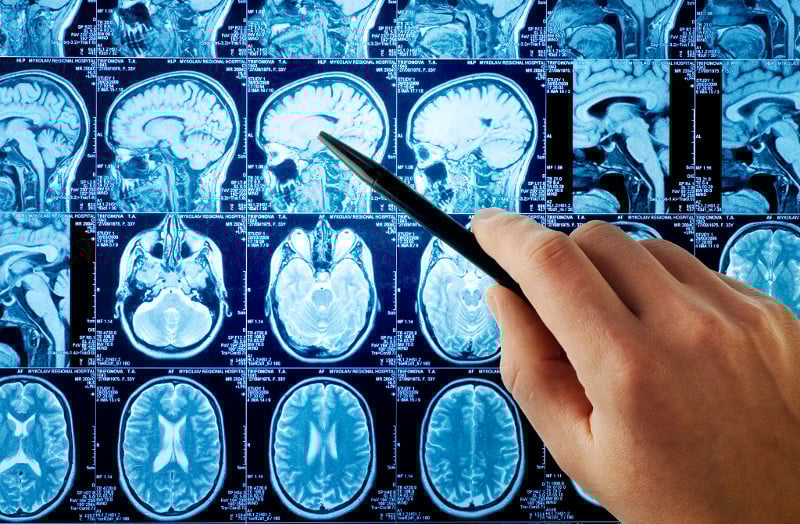

De nombreux examens ont été faits chez plusieurs enfants, (Electroencéphalogramme, Résonance Magnétique Cérébrale, PET-Scan, SPECT, Etude du caryotype, Recherches métaboliques…), aucun n’a donné de résultats significatifs jusqu’ici pour tenter d’expliquer la maladie.